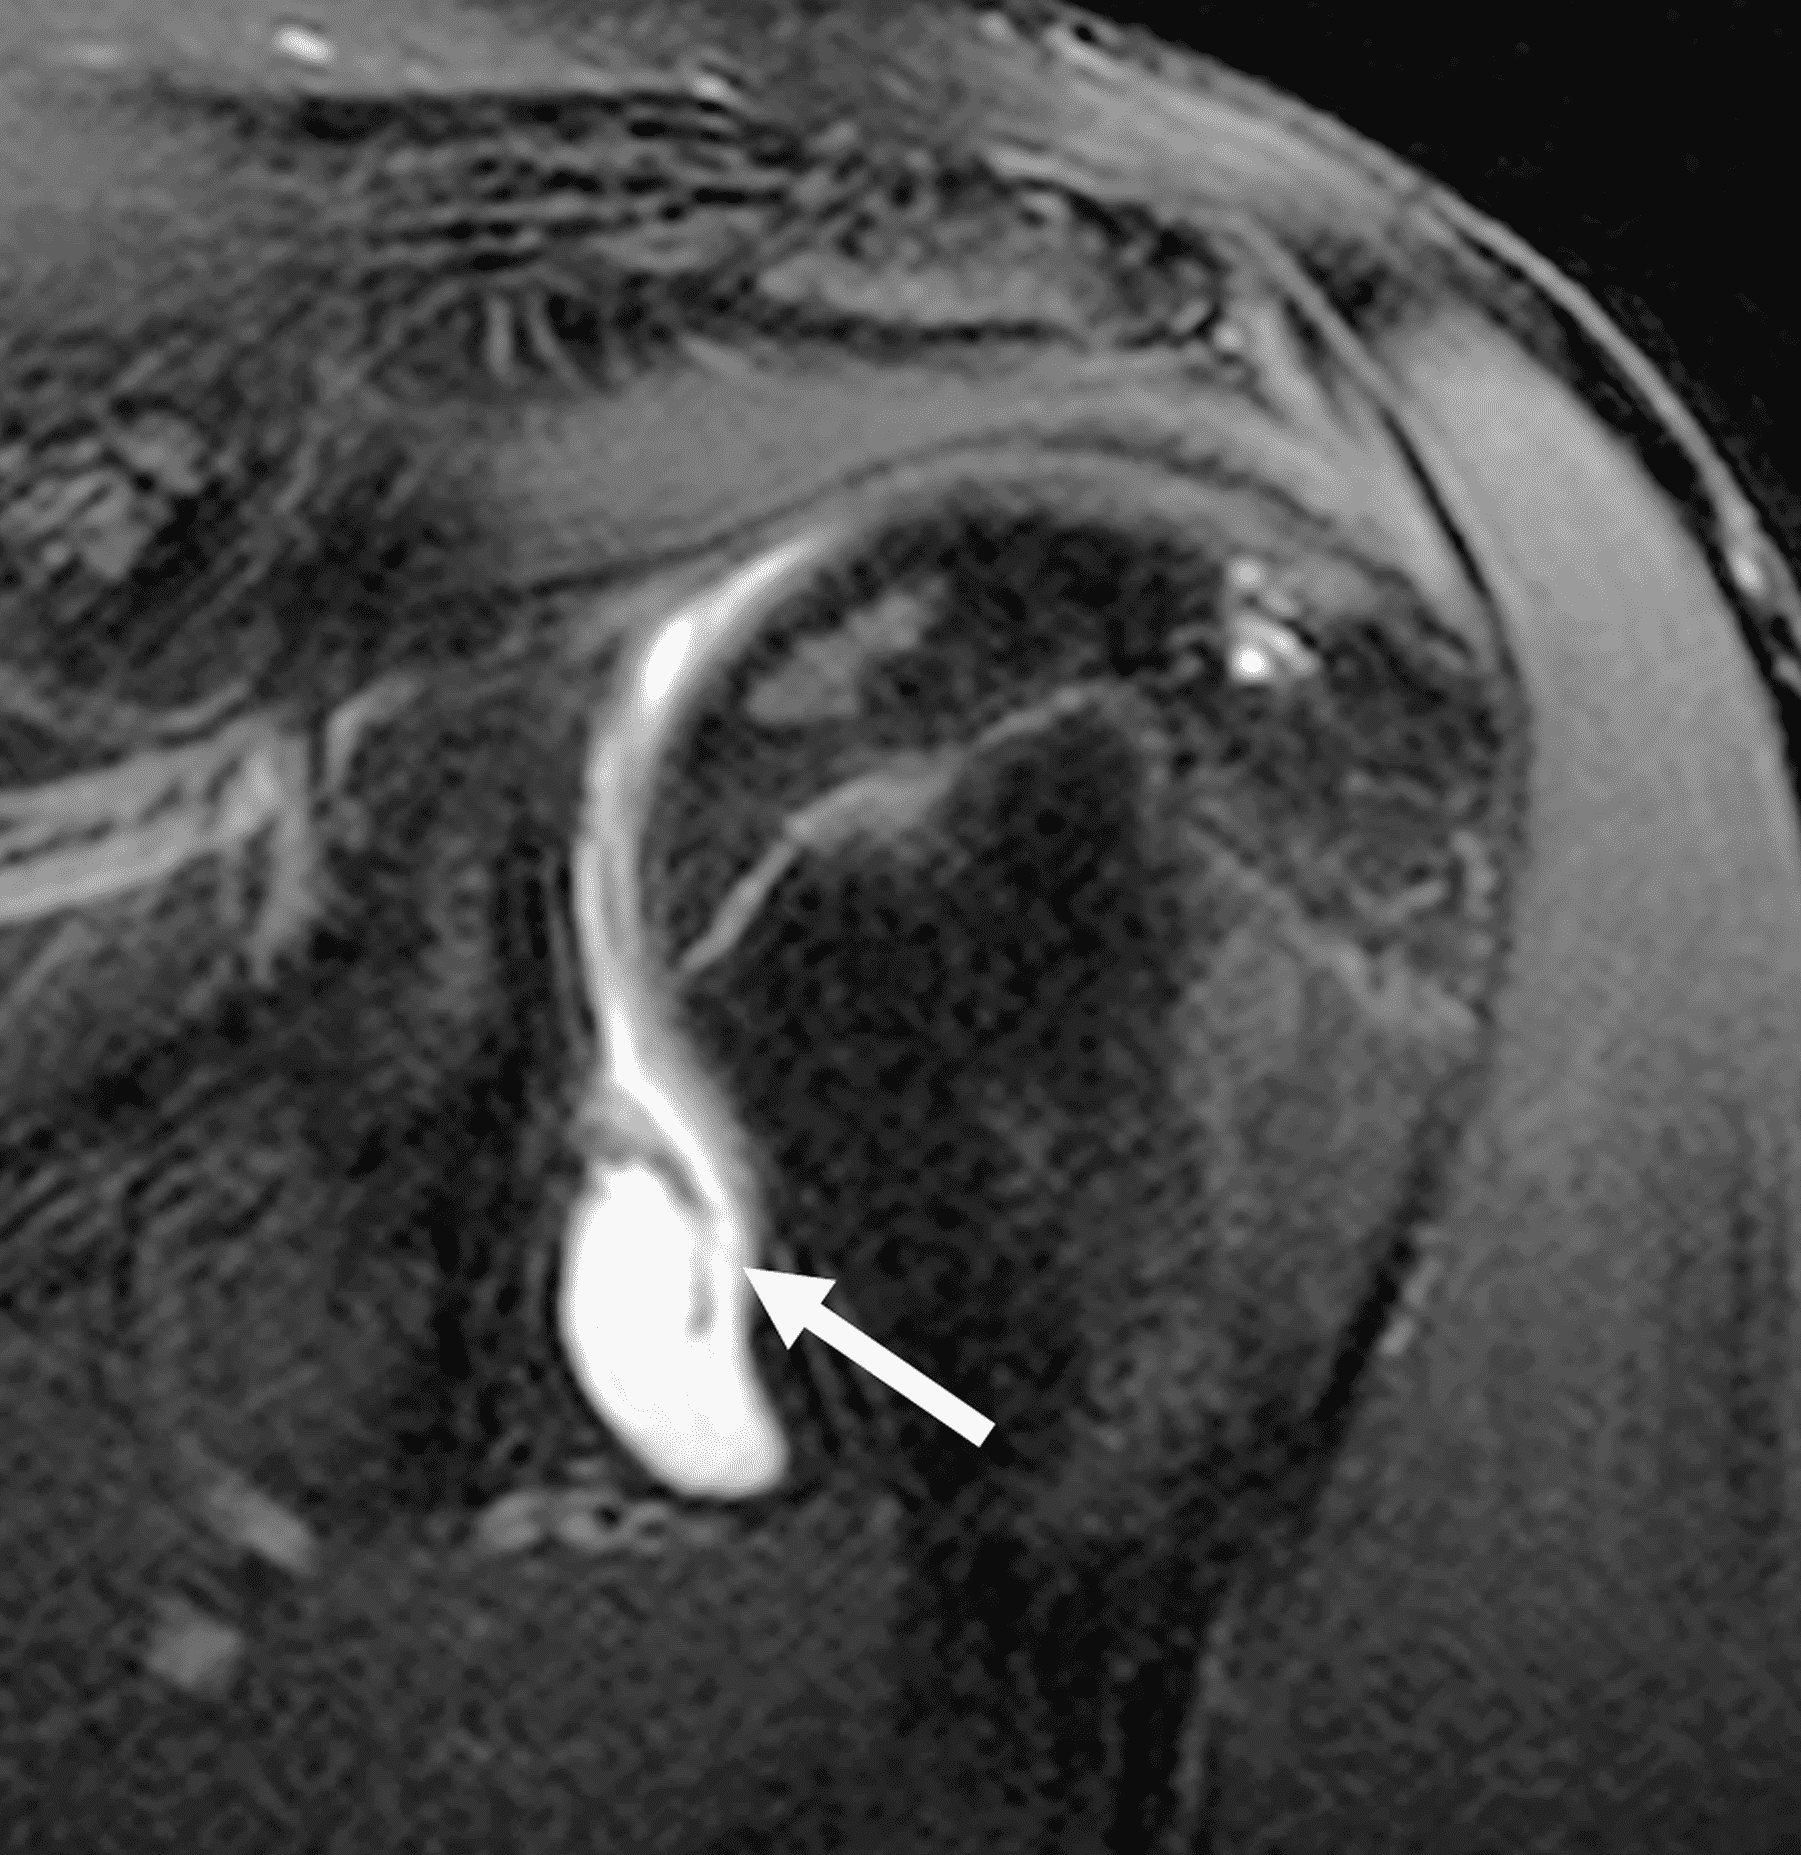

20 year old right-handed hitting college baseball player with left shoulder injury. Fat-suppressed proton-density-weighted axial images at the mid (1A) and inferior (1B) left glenohumeral joint are provided. What are the findings? What is your diagnosis?

Figure 2: The axial images (2A and 2B) demonstrate findings of a posterior glenohumeral instability injury including posterior to posteroinferior capsulolabral tearing and pericapsular edema (solid arrows) and an anteromedial humeral head impaction injury (dashed arrows).

Batter’s shoulder (posterior glenohumeral instability).